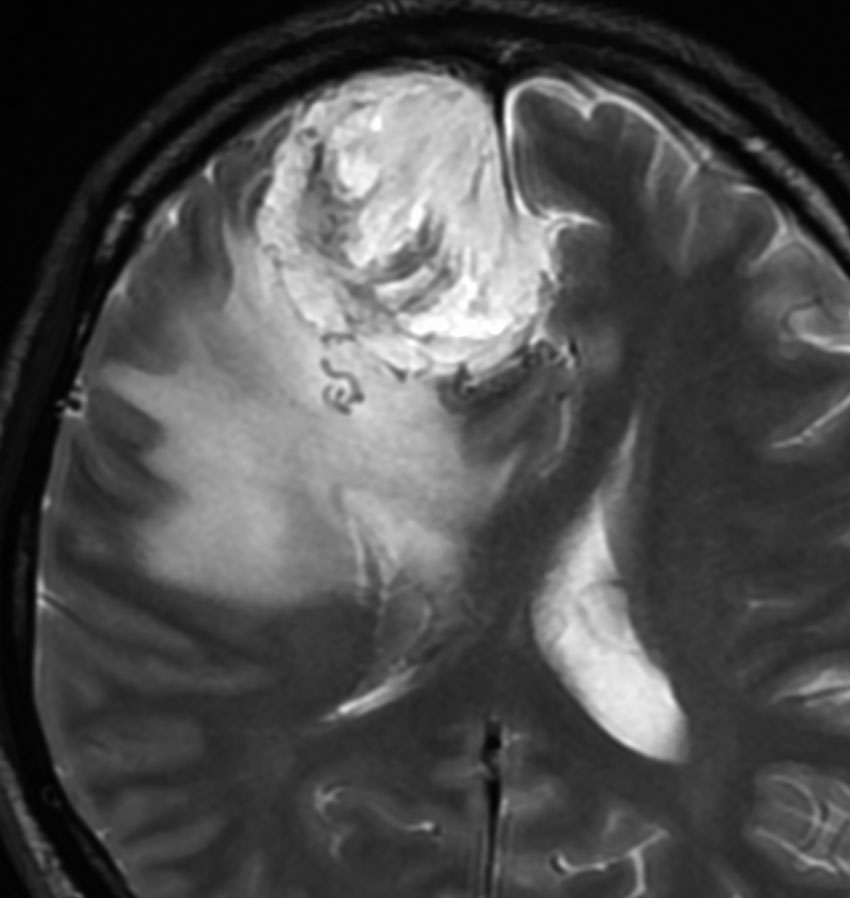

angiomatous meningioma WHO grade 1 血管腫様髄膜腫

術前検査ではまるで膠芽腫のような画像です。でも,開けてみれば髄膜腫ということはすぐにわかる肉眼所見です。硬膜の至る所から腫瘍血管が流入して出血性腫瘍です。

多数の小血管から構成される組織像です。右のvimentin染色は陽性です。

核小体明瞭な大小不同な類円形核からなる細胞境界が不明瞭な腫瘍細胞がみられ,ヘモジデリン貪食マクロファージも認められます。MIB-1染色率は2-3%でグレード1です。